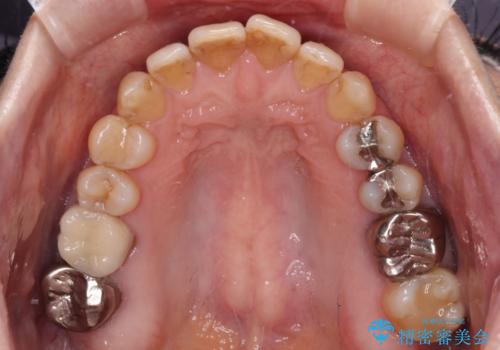

- 上下前歯のデコボコと、奥歯の銀歯を気にして来院された患者様です。

概ね歯列が整ったところで銀歯の全てをセラミッククラウンなどに置き換え、その後インビザラインを1セット使用して仕上げていくこととしました。